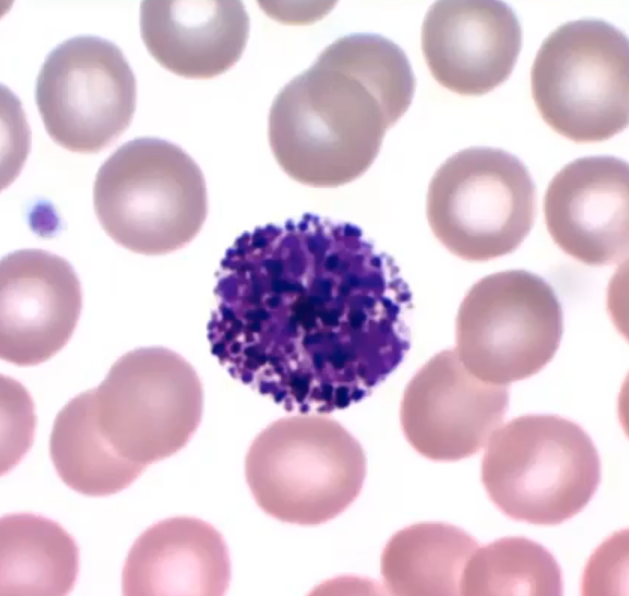

Name

Basophil

Rarest WBC

slows down blood clotting

Start inflammatory response